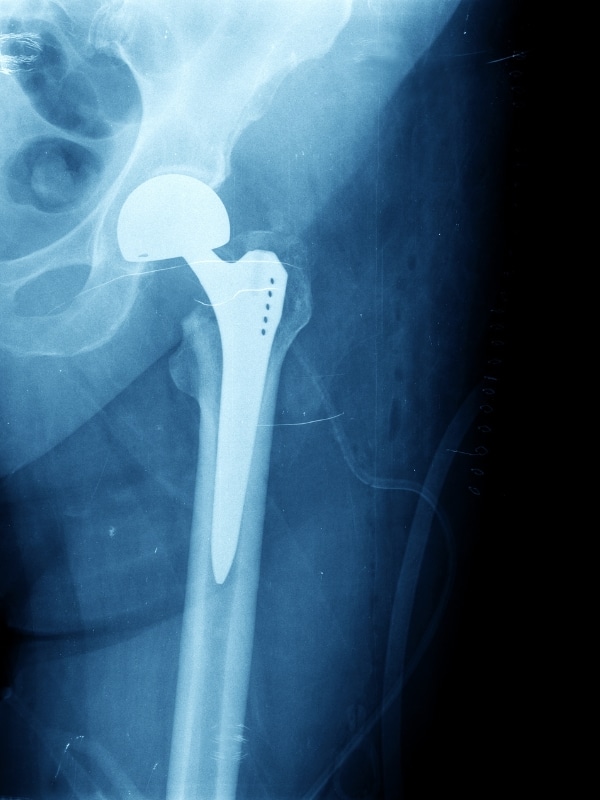

Endoprotezoplastyka biodra pozwala zlikwidować przewlekły ból, przywrócić ruchomość i umożliwia wieloletnie, stabilne funkcjonowanie stawu.

Nasze podejście opiera się na wyborze najbardziej efektywnych i jednocześnie możliwie mało inwazyjnych technik, zgodnych z najnowszymi zaleceniami ortopedycznymi. Endoprotezy dobieramy indywidualnie – korzystamy głównie z implantów bezcementowych o wysokiej trwałości, wykonanych z komponentów metalowych, polietylenowych lub ceramicznych.